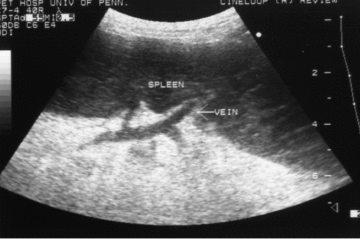

Ultrasongraphic appearence of splenic torsion?

Splenomegally, diffusely hypoechoic (also seen with necrosis and infarction)

6/7 dogs had hilar perivenous hyperechoic triangle

chronic may demonstrate gas shadowing

Absence of blood flow on color flow doppler US